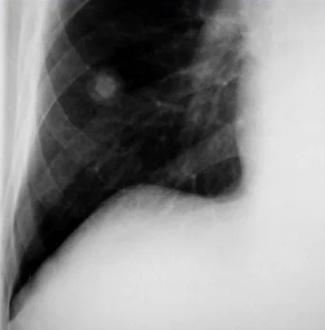

Derrame pericárdico severo da imagen en botellón en la radiografía de tórax. (ENAM EXTRA 2021)